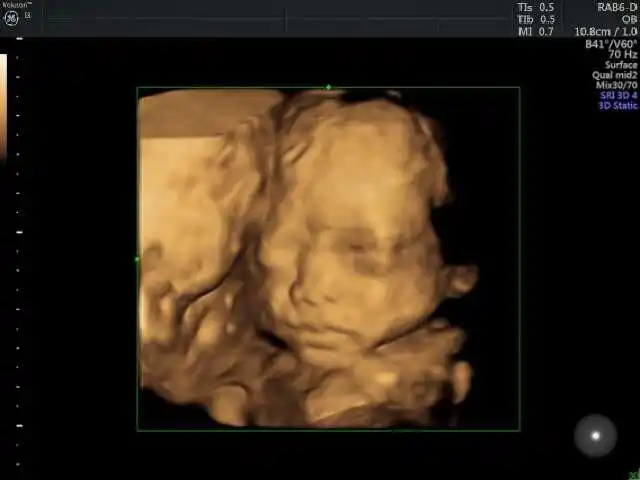

四维彩超的重要性

宝宝的四维彩超照